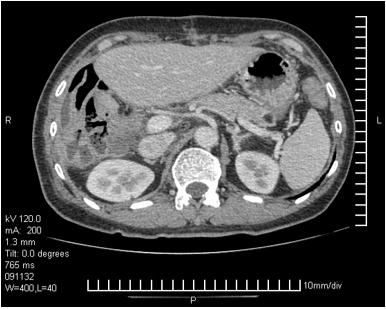

影像学检查

入院时胸、腹、盆腔等影像学检查及CT/MRI片子

升结肠癌肝转移(cT3N0M1b, IVb期)

患者男性,56岁,确诊右半结肠癌伴肝脏多发转移,确诊时临床危险评分(CRS)4分(具有同时性肝转移、多个转移灶、最大病灶长径>5cm、CEA>200ng/ml)属于高危患者[1]。按照ESMO推荐的对于结肠癌肝转移患者的评估标准该患者属于技术上难切除,预后差的患者,应该选取最佳全身治疗进行转化治疗[2, 3]。患者并未出现梗阻、明显出血、穿孔或其他原发肿瘤引起的症状,因此按照NCCN指南推荐全身治疗而不建议初始切除原发灶[4]。患者年轻、一般情况可,原发灶位于右半结肠,且其KRAS基因为突变型,因此推荐选择三药联合化疗(FOLFOXIRI),如患者经济上可以承受也可考虑三药或双药(FOLFOX或FOLFIRI)联合贝伐单抗[5, 6]。关于右半结肠癌的一线治疗推荐,2017版NCCN指南明确指出不考虑使用EGFR抗体;而ESMO指南对于RAS野生型、Braf野生型患者,当以肿瘤减灭为目的时首选两药联合+EGFR抗体,次选三药联合或不联合贝伐单抗。针对一线化疗对比化疗联合西妥昔单抗的左右半分析,共有两项Ⅲ期临床研究的回顾性分析结果和一项中山大学肿瘤防治中心的回顾性研究结果,在CRYSTAL、TAILOR和我们的研究中都显示化疗联合西妥昔单抗对比单纯化疗有效率、PFS和OS均未呈现显著提高[7, 8]。另外两项头对头比较双药联合贝伐单抗或西妥昔单抗的临床研究FIRE3和80405都显示两者在有效率方面无显著的差别[9]。因此如果该患者为RAS野生型仍不建议首选EGFR抗体治疗。

2程化疗后展示的患者肝脏CT无明显改变,评价为PD的原因不明。若患者因肝脏或其他部位出现新发病灶出现了病情进展,可考虑二线采用FOLFIRI联合贝伐单抗,4程化疗后肝脏病灶明显减少、缩小,评价为PR。因贝伐单抗使用后需暂停6周以上才能进行手术,因治疗间隔太长,建议该患者在停用贝伐单抗期间进行FOLFIRI方案化疗2至3疗程。手术切除原发灶和肝转移灶,病理已确认。其后患者进行了术后辅助化疗4程,患者术前行化疗4程,仅出现Ⅱ度骨髓抑制,根据NCCN指南术后可建议其行8程FOLFIRI方案或2-3程FOLFIRI方案加6-5程FOLFIRI联合贝伐单抗方案化疗,达到共6个月的围手术期化疗。

患者肝内发现6个病灶,位于右肝,有一个大肿瘤临近门静脉主干,K-RAS为突变型,术前的转化化疗有一个PR的良好反应,所以这个患者的治疗目标还是应该是治愈。所以,治疗选择一定是根治性的治疗。由于肿瘤靠近门静脉主干,手术中外科医生做了最大努力使得病灶达到肉眼R0切除,实属不易。但术后半年不到时间出现复发,是否与未采用磁共振评估肝转移灶有关,值得商榷。最近韩国有一项多中心回顾研究提示对于临床完全缓解的肠癌肝转移患者,普美显-磁共振漏诊率明显低于增强CT(22.0% vs. 64.8%)。因此,还是要强调肝脏转移瘤常规行磁共振检查。